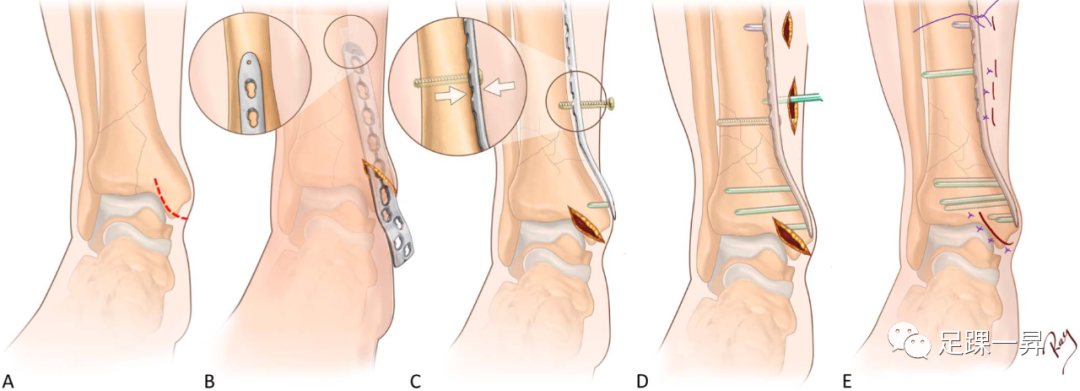

Pilon骨折手术的标准前路方法已得到充分描述。后侧入路也有很好的描述,可以在传统固定中发挥补充作用,直接复位和/或固定特定骨折碎片,并松解嵌顿的软组织结构。部分关节(OTA/AO型-43B)的手术入路相对简单,由移位的关节碎片区域决定。完全性关节(OTA/AO型-43C)损伤需要根据原发骨折线的位置以及关节面压缩区域采用个体化方法。已经提出了各种详细描述骨折复位和固定的手术技术。通常,具体的前路切口和肌腱间隔是基于前外侧(Chaput)和内侧骨折块之间骨折线的位置; 通过这些骨折块的间隙可以进入后方和进入压缩区域(图5)。直接内侧入路可用于支撑内侧柱避免内翻塌陷。

△图示Pilon骨折的术中照片,其中Chaput骨块和内侧骨块之间的骨折线被“翻书样打开”,以便于更靠后地接近压缩区域。一旦后侧复位工作完成,将Chaput骨块和内侧骨块复位并进行固定。

一项关于Pilon骨折手术入路的系统综述发现,与后外侧和前内侧入路相比,直接前路和内侧入路的并发症发生率较低,包括伤口并发症和骨不连。在另一项评估手术入路对Pilon骨折术后感染风险影响的研究中,未检测到相关性。已报告的并发症发生率差异可能是由于软组织的状况和血供所致。每种骨折和患者都必须单独考虑,以优化关节复位和软组织愈合。

△图示胫骨远端水平的轴位切口示意图,描绘了标准手术入路的间隔,包括前内侧和扩展前内侧(A)、前外侧(B)、后外侧腓骨(C)、后外侧胫骨(D)、后内侧(E)和直接内侧(F)。